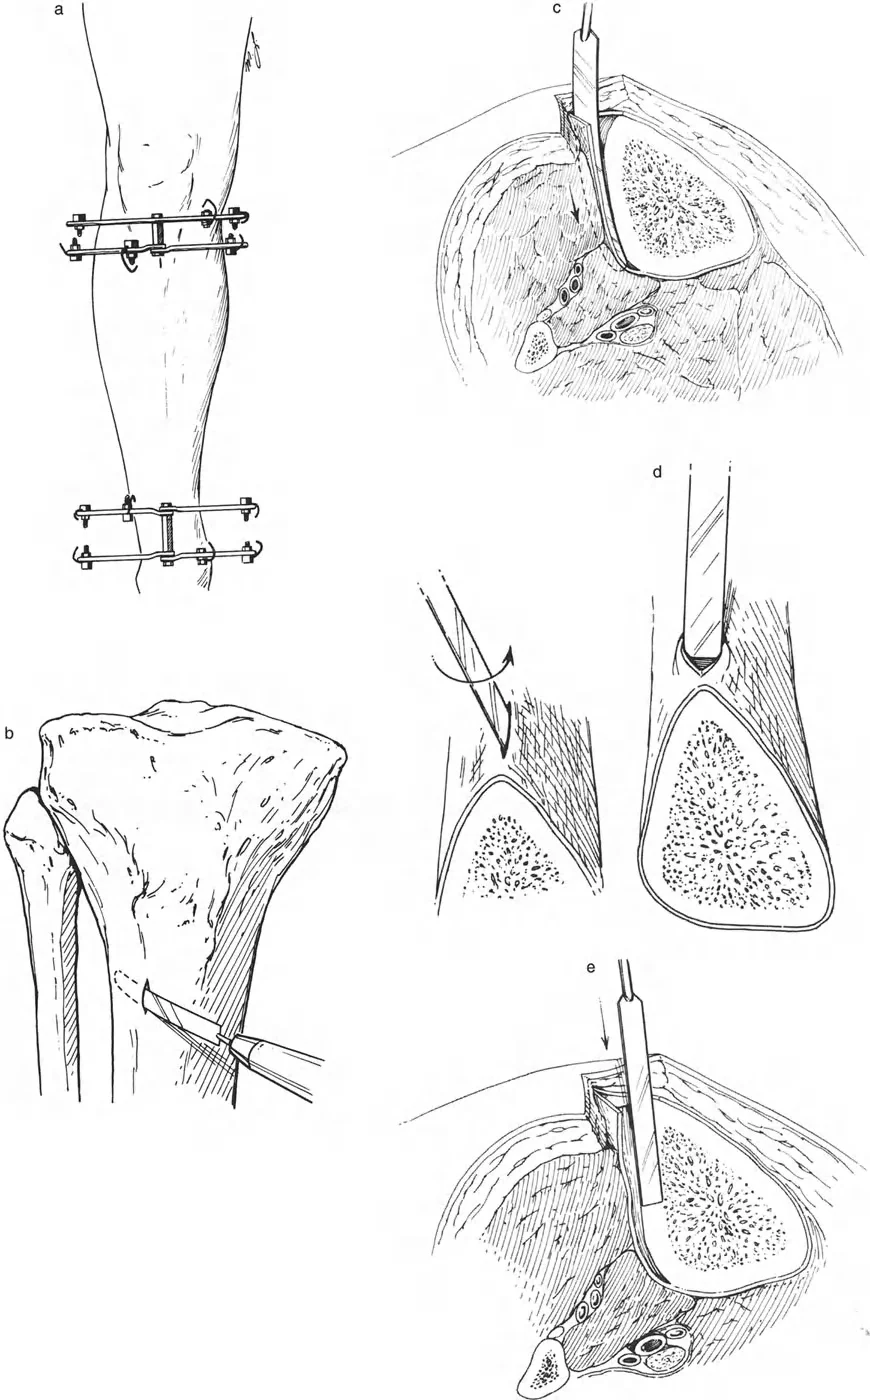

المفصلات القريبة من المفصل وقواعد قطع العظم (Osteotomy Rules)

عند التعامل مع التشوهات الواقعة بالقرب من خط المفصل - مثل التقوس الشديد في الجزء العلوي من الساق (مرض بلونت) أو التشوه الفحجي في الجزء السفلي من عظم الفخذ - يصبح وضع الجهاز مقيدًا هندسيًا. إن المتطلبات البيولوجية للحفاظ على كبسولة المفصل، وتجنب وضع الأسلاك داخل المفصل، ومنع التهاب المفاصل القيحي، غالبًا ما تجبر الجراح على وضع الحلقة المرجعية على مستوى مختلف تمامًا عن مركز دوران الانحراف (CORA) الفعلي.

تحدي مركز دوران الانحراف (CORA) القريب من المفصل

لمطابقة مفصلة المثبت الخارجي مع المستوى الدقيق لمركز دوران الانحراف (CORA)، يجب غالبًا بناء المفصلة فوق أو تحت مستوى الحلقة الفعلية. يُعرف هذا في مبادئ بالي باسم تجميع المفصلة القريبة من المفصل (juxta-articular hinge assembly).

إذا كان مركز دوران الانحراف (CORA) يقع بالقرب من خط المفصل، فإن وضع حلقة إليزاروف القياسية عند هذا المستوى بالضبط مستحيل دون انتهاك مساحة المفصل أو شد الهياكل الكبسولية الحيوية. لذلك، يتم تثبيت الحلقة المرجعية بالعظم الكثيف أو العظم الطويل المتاح، ويتم بناء آلية المفصلة باستخدام قضبان ملولبة، ولوحات توصيل، ودعامات. ثم يتم "إنزالها" (أو رفعها) لتتطابق تمامًا مع مركز دوران الانحراف (CORA) الهندسي الحقيقي.

قواعد بالي لقطع العظم (Osteotomy Rules) في وضع الأجهزة

فهم قواعد بالي لقطع العظم أمر لا غنى عنه لتخطيط الإطار:

- قاعدة قطع العظم 1: عندما يمر قطع العظم ومحور تصحيح الانحراف (ACA) كلاهما عبر مركز دوران الانحراف (CORA)، فإن نهايات العظم ستنحرف دون ترجمة (انزياح). يتم استعادة المحور الميكانيكي، وتظل نهايات العظم متقاربة تمامًا، مما يخلق تصحيحًا كلاسيكيًا "إسفينيًا مفتوحًا" أو "إسفينيًا مغلقًا".

- قاعدة قطع العظم 2: عندما يمر محور تصحيح الانحراف (ACA) عبر مركز دوران الانحراف (CORA)، ولكن يتم إجراء قطع العظم على مستوى مختلف (غالبًا بسبب ضعف جودة العظم عند CORA أو مشاكل في الجلد)، فإن نهايات العظم ستنحرف وتخضع لترجمة محسوبة ومقصودة لإعادة محاذاة المحور الميكانيكي.

- قاعدة قطع العظم 3: (للاكمال) عندما يمر قطع العظم عبر مركز دوران الانحراف (CORA)، ولكن يتم وضع محور تصحيح الانحراف (ACA) خارج CORA، سيتم إنشاء تشوه ترجمة جديد، وهو خطأ شائع في وضع المفصلات غير المخطط له جيدًا.

في المنشآت القريبة من المفصل، غالبًا ما نعتمد على قاعدة قطع العظم 2. نظرًا لأنه لا يمكننا قطع العظم بأمان عند خط المفصل تمامًا (مركز دوران الانحراف CORA)، فإننا نقطع العظم في مستوى أدنى في منطقة الميتافيسيس. بعد تحقيق التصحيح الزاوي عبر المفصلات (محور تصحيح الانحراف ACA)، يتم إعادة محاذاة خطوط المحور الميكانيكي بشكل مثالي، ولكن نهايات العظم في موقع قطع العظم تتحرك بالنسبة لبعضها البعض.

قيود الأسلاك والدبابيس في القاعدة 2

لتحقيق هذه الترجمة الضرورية والمقصودة بسلاسة باستخدام إطار دائري كامل الأسلاك، يلزم استخدام أسلاك الزيتون المعاكسة (counter-opposed olive wires). تعمل أسلاك الزيتون كقوى سحب ديناميكية، تسحب قطعة العظم على طول الحلقة أثناء فتح المفصلات. بدون أسلاك الزيتون، سيبقى العظم ثابتًا بينما تتحرك الحلقة عبر الأنسجة الرخوة، مما يسبب نخرًا شديدًا في الجلد.

على العكس من ذلك، إذا تم استخدام دبابيس نصفية (مسامير شانز)، فإنها تقيد العظم بطبيعتها بالحلقة. نظرًا لأن الدبابيس النصفية هي أذرع صلبة (مثبتة من طرف واحد بالحلقة ومغروسة في العظم من الطرف الآخر)، فإنها لا تسمح للعظم بالانزلاق على طول محور السلك. هذا يجعل أسلاك الزيتون غير ضرورية للترجمة في منشآت الدبابيس النصفية، ولكنه يتطلب من الجراح التأكد من أن الدبابيس النصفية قوية بما يكفي (عادةً دبابيس بقطر 5 مم أو 6 مم مطلية بهيدروكسي أباتيت) لتحمل لحظات الانحناء الناتجة عن الترجمة.

نصائح جراحية للمنشآت القريبة من المفصل